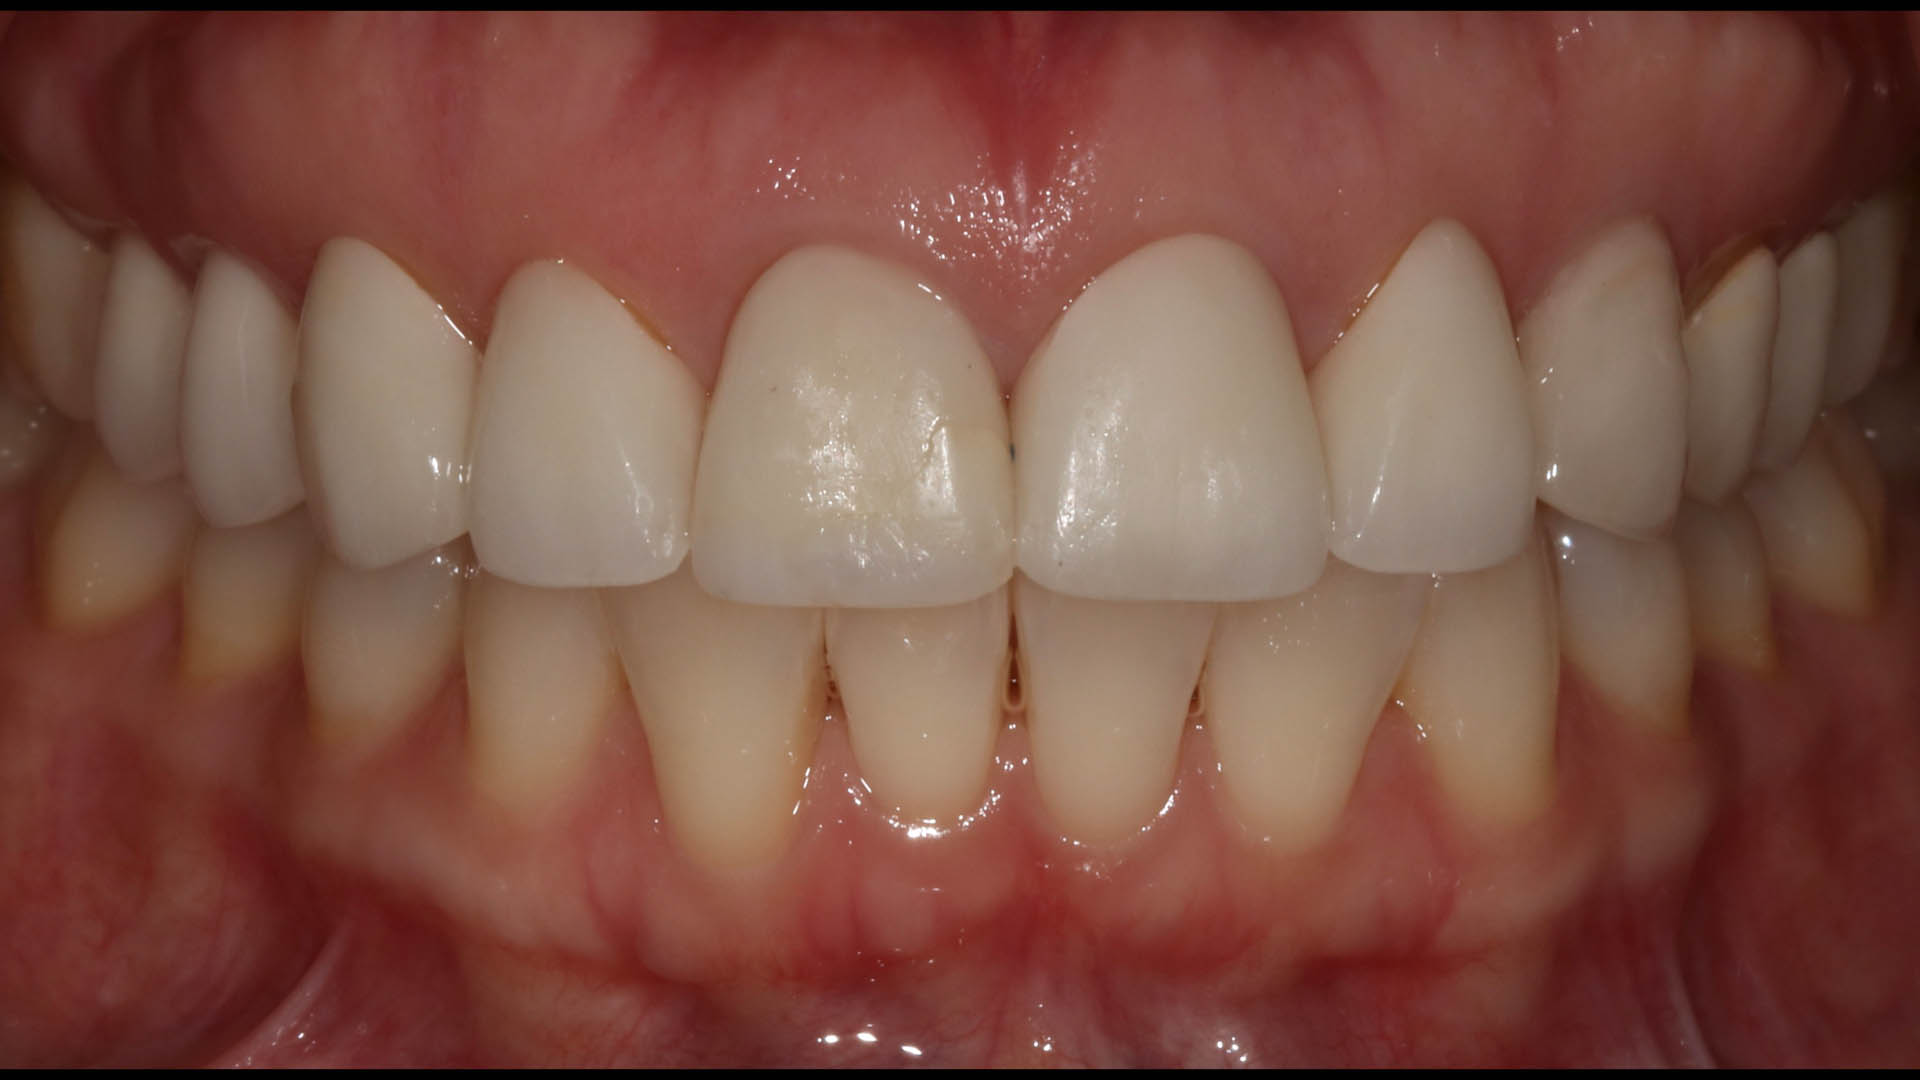

Take a glimpse into the magic of Coral Gables Dentistry through our before and after pictures. See firsthand the incredible smile makeover transformations that have brought confidence and joy to our patients.